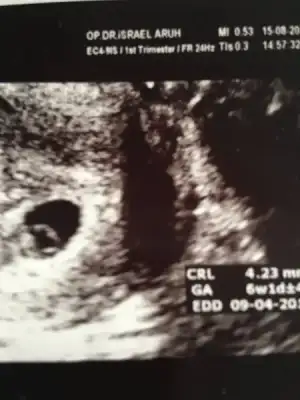

Bu arada ben de gördüm miniğimi kalp atışını da duydum. Çok güzel bir duygu. Sağ salim devam eder umarım. Ultrason ölçümüne göre 6+1 sat a göre 6+5 doktorum sat esas almalıyız dedi. Allah isteyen herkese kısmet etsin. Hepimizin gebelikleri sağ salim geçsin inşallah.

Eklentiler

• image.webp

image.webp

13,5 KB · Görüntüleme: 66